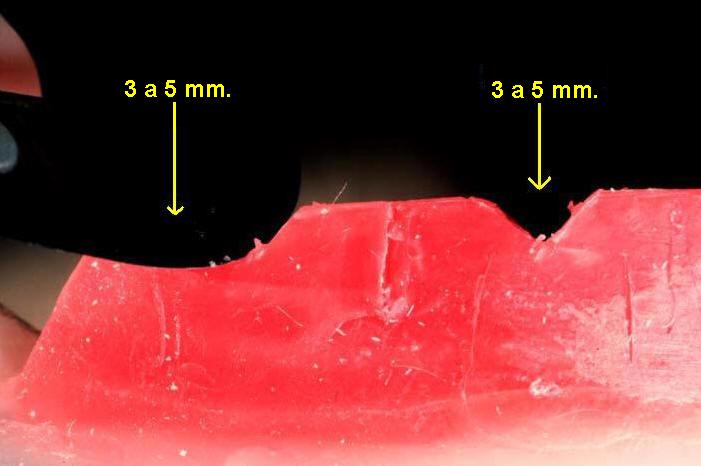

- Realice escotaduras en "V" en el rodete

inferior y superior de 3 a 5 mm de profundidad; siempre de tras de las marcas

de las guías caninas. (Ver imagen inferior)